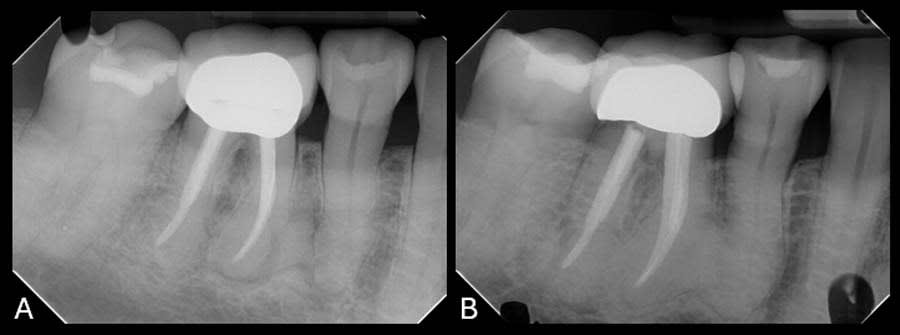

Upon review of the FMX, multiple quadrants of hypercementosis were noted, including all mandibular quadrants and the maxillary left quadrant, and an electric pulp test of the mandibular right posterior quadrant demonstrated vital pulps, with the exception of tooth No. 30 (Figure 1). Teeth Nos. 29 and 30 had no mobility and were percussion negative with periodontal pocket depths buccally of 3 mm and 2 mm and distally of 3 mm and 4 mm, respectively. There was no pain on percussion of tooth No. 31. From the periapical radiographs, the roots of teeth Nos. 29 and 30 were noted to be grossly thickened, bulbous, and blunted due to a fairly symmetrical deposition of a radiopaque material on their surfaces (Figure 2, right). Also noted, both the second premolar and first molar had obvious concrescence of cementum, most pronounced at the first molar (Figure 2, right). In addition, tooth No. 30 incipient PDL space widening and generalized posterior alveolar osseous bone loss were also noted.

To establish a differential diagnosis, in addition to testing both teeth Nos. 29 and 30 for endodontic/periodontal disease, the clinician reviewed the patient’s systemic health and referenced a previous FMX captured in 2018, which demonstrated a progression of cementum deposition (Figure 2, left). Cementum deposition progression to concrescence of Nos. 25/26 could also be noted (Figure 3).